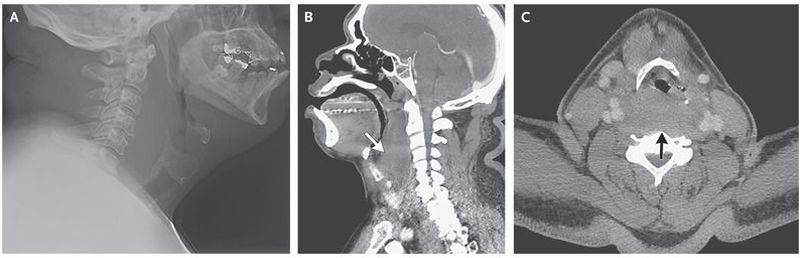

A 56-year-old man presented to the emergency department with a 5-hour history of throat swelling and pain and difficulty breathing that was exacerbated by supine positioning; he had not had any obvious antecedent trauma. His medical history included prostate cancer, hypertension, hyperlipidemia, deep-vein thrombosis, and stroke. Medications included warfarin (presumably for deep-vein thrombosis), antihypertensive agents, and a statin. He was afebrile, and the physical examination was notable for minor swelling of the posterior oropharynx. Laboratory studies revealed a normal white-cell count, an international normalized ratio of more than 11, a prothrombin time of more than 120 seconds, and an activated partial-thromboplastin time of 127 seconds. Radiography of the neck revealed marked soft-tissue swelling that was causing mass effect on the airway (Panel A); the findings on a subsequent computed tomographic scan of the neck were consistent with a retropharyngeal hematoma, which was probably caused by supratherapeutic anticoagulation (Panel B shows the sagittal view, and Panel C the axial view; the arrow in each panel indicates the hematoma). Transnasal laryngoscopy revealed a bulging posterior pharynx but a patent airway. The patient was administered 6 units of fresh-frozen plasma and was admitted to the intensive care unit for observation. His coagulopathy resolved, as did his symptoms, and he was discharged 4 days after admission.